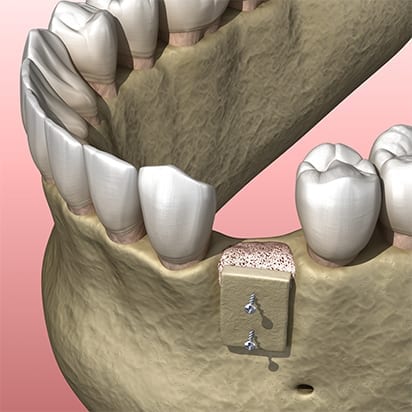

Depending on your particular case we will use either particle graft material, or block grafts, or both. Particle graft material is packed into and around an area with insufficient bone, whereas block grafts are screwed into the jawbone.

Combination of particle graft and block graft material: